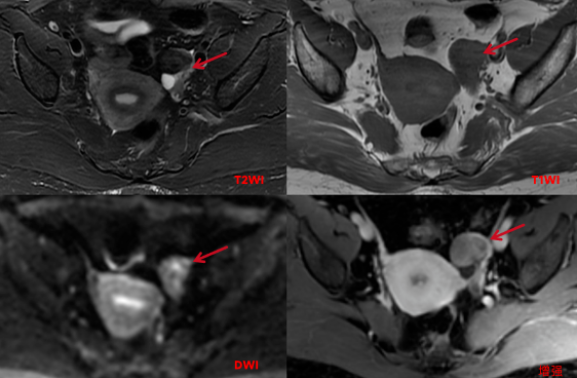

影像表现:

盆腔MRI平扫及增强:左侧附件区可见稍长T1短及稍短T2信号,大小约25x30x30mm,T2WI压脂像呈稍低信号,边界清楚,边缘较光滑,DWI呈周边不均匀稍高信号,中心信号稍低, 增强扫描不均匀中等强化,其后方另见多个小囊状长T2信号,增强扫描病变囊壁稍厚,光滑,轻微强化。

影像诊断:左侧附件区囊实性占位,倾向良性可能性大,Brenner瘤或卵泡膜纤维瘤可能性大,建议临床活检。

鉴别诊断:子宫阔韧带肌瘤并钙化、颗粒细胞瘤